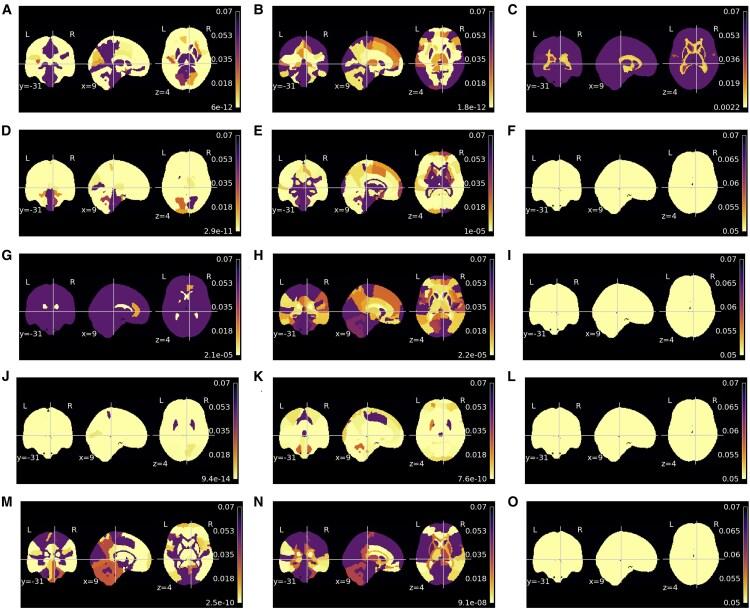

Brain age gap estimation (BrainAGE), the difference between predicted brain age and chronological age, might be a putative biomarker aiming to detect the transition from healthy to pathological brain ageing. The biomarker primarily models healthy ageing with machine learning models trained with structural magnetic resonance imaging (MRI) data. BrainAGE is expected to translate the deviations in neural ageing trajectory and has been shown to be increased in multiple pathologies, such as Alzheimer's disease (AD), schizophrenia and Type 2 diabetes (T2D). Thus, accelerated ageing seems to be a general feature of neuropathological processes. However, neurobiological constraints remain to be identified to provide specificity to this biomarker. Explainability might be the key to uncovering age predictions and understanding which brain regions lead to an elevated predicted age on a given pathology compared to healthy controls. This is highly relevant to understanding the similarities and differences in neurodegeneration in AD and T2D, which remains an outstanding biological question. Sensitivity maps explain models by computing the importance of each voxel on the final prediction, thereby contributing to the interpretability of deep learning approaches. This paper assesses whether sensitivity maps yield different results across three conditions related to pathological neural ageing: AD, schizophrenia and T2D. Five deep learning models were considered, each model trained with different MRI data types: minimally processed T-weighted brain scans, and corresponding grey matter, white matter, cerebrospinal fluid tissue segmentation and deformation fields (after spatial normalization). Our results revealed an increased BrainAGE in all pathologies, with a different mean, which is the smallest in schizophrenia; this is in line with the observation that neural loss is secondary in this early-onset condition. Importantly, our findings suggest that the sensitivity, indexing regional weights, for all models varies with age. A set of regions were shown to yield statistical differences across conditions. These sensitivity results suggest that mechanisms of neurodegeneration are quite distinct in AD and T2D. For further validation, the sensitivity and the morphometric maps were compared. The findings outlined a high congruence between the sensitivity and morphometry maps for age and clinical group conditions. Our evidence outlines that the biological explanation of model predictions is vital in adding specificity to the BrainAGE and understanding the pathophysiology of chronic conditions affecting the brain.

脑龄差距估计(BrainAGE),即预测脑龄与实际年龄之间的差异,可能是一种旨在检测从健康脑老化向病理性脑老化转变的潜在生物标志物。该生物标志物主要通过使用结构磁共振成像(MRI)数据训练的机器学习模型来模拟健康老化。BrainAGE有望转化神经老化轨迹中的偏差,并且已被证明在多种疾病中会增加,如阿尔茨海默病(AD)、精神分裂症和2型糖尿病(T2D)。因此,加速老化似乎是神经病理过程的一个普遍特征。然而,仍有待确定神经生物学限制因素,以便为该生物标志物提供特异性。可解释性可能是揭示年龄预测以及理解与健康对照相比,在特定病理情况下哪些脑区导致预测年龄升高的关键。这对于理解AD和T2D中神经退行性变的异同至关重要,这仍然是一个悬而未决的生物学问题。敏感性图通过计算每个体素对最终预测的重要性来解释模型,从而有助于深度学习方法的可解释性。本文评估了敏感性图在与病理性神经老化相关的三种情况下(AD、精神分裂症和T2D)是否会产生不同的结果。考虑了五个深度学习模型,每个模型使用不同的MRI数据类型进行训练:最少处理的T加权脑扫描,以及相应的灰质、白质、脑脊液组织分割和变形场(空间归一化后)。我们的结果显示,在所有疾病中BrainAGE均增加,但其平均值不同,在精神分裂症中最小;这与在这种早发性疾病中神经损失是次要的这一观察结果一致。重要的是,我们的研究结果表明,所有模型的敏感性(即区域权重指标)随年龄而变化。一组区域在不同情况下显示出统计学差异。这些敏感性结果表明,AD和T2D中的神经退行性变机制截然不同。为了进一步验证,比较了敏感性图和形态测量图。研究结果表明,年龄和临床组条件下的敏感性图与形态测量图高度一致。我们的证据表明,模型预测的生物学解释对于增强BrainAGE的特异性以及理解影响大脑的慢性疾病的病理生理学至关重要。